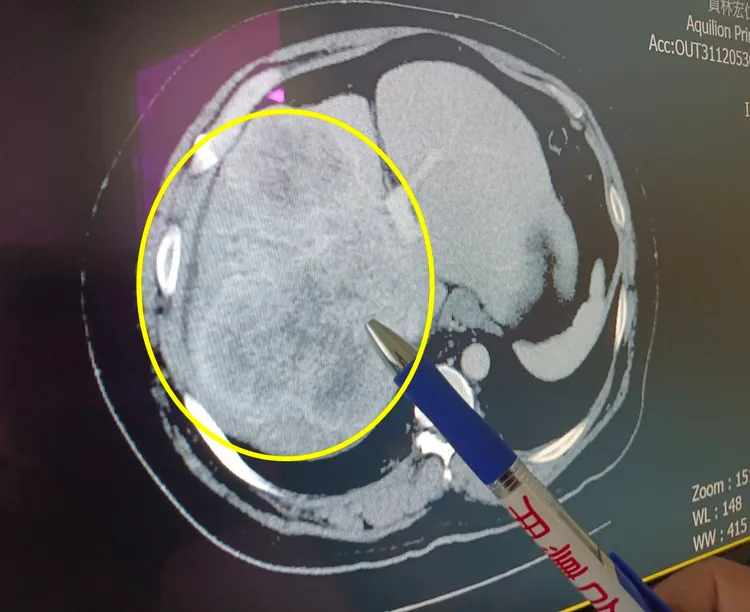

童醫院一般外科醫師余積琨診察後,進行電腦斷層等相關精密檢查,發現賴男肝腫瘤約15公分大(肝癌第三期),且腫瘤位置險峻靠近血管,若手術有高度肝衰竭風險。賴先生與家人相信童醫院醫療團隊,決定進行擴大右肝切除手術。

進行手術前影像檢查(腫瘤部位為黃色圓圈處)。童醫院提供